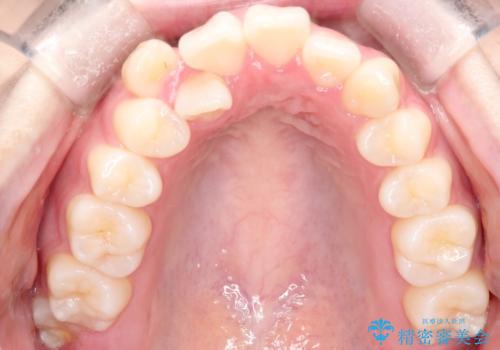

- 4番の歯を4本抜歯をし、上顎にマイクロインプラントを2本埋入し、遠心移動を行いました。

主訴のオープンバイトは改善し、抜歯をしたことで前歯が下がり綺麗になりました。抜歯矯正でしたが1年2か月という短い期間で終了しました。